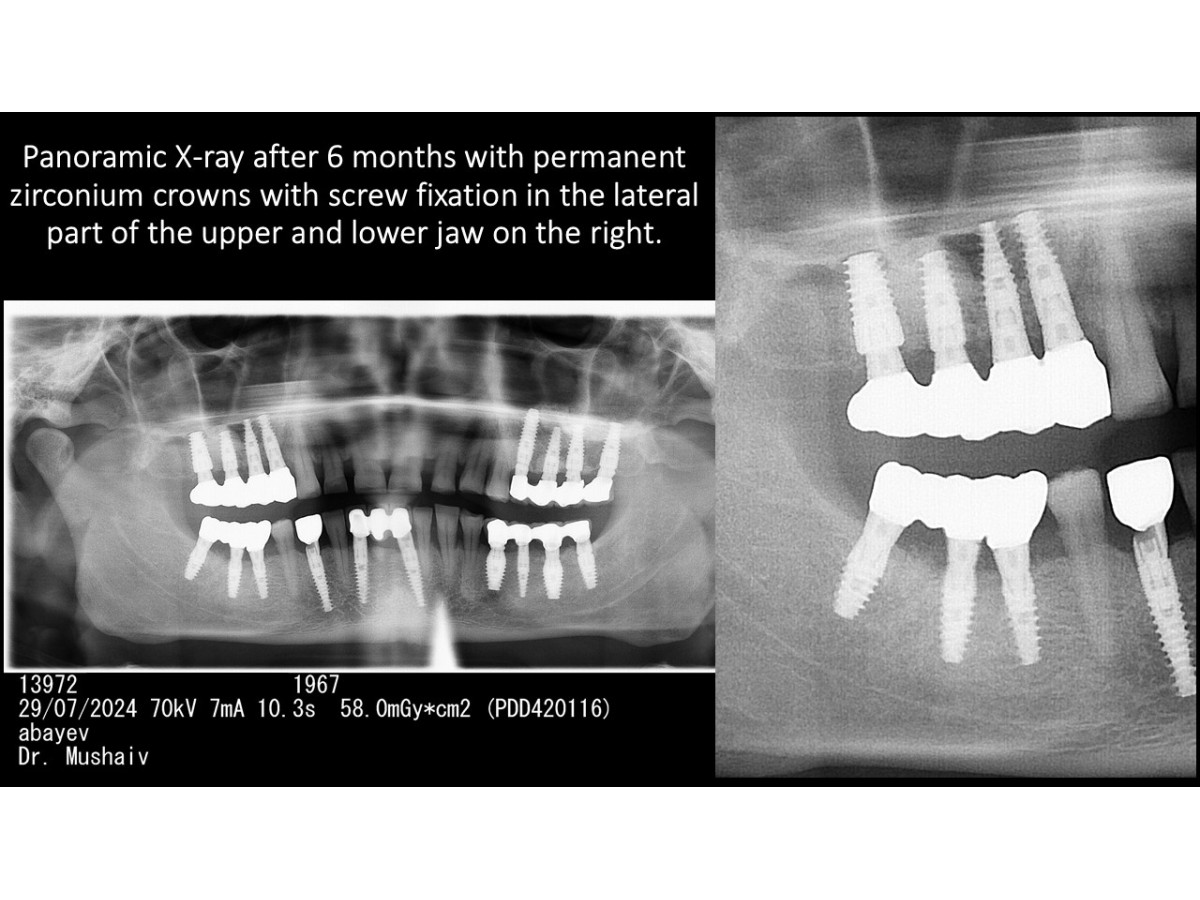

Direct implantation with immediate loading & FOLLOW-UP 7 YEARS AFTER SURGERY

Clinical case: Direct implantation with immediate loading, bone augmentation, sinus lifting and soft tissue monitoring. Follow-up 7 years after surgery

Dentist: DDS PhD Ilia Mushayev/Sidhedent, DMi (Israel)